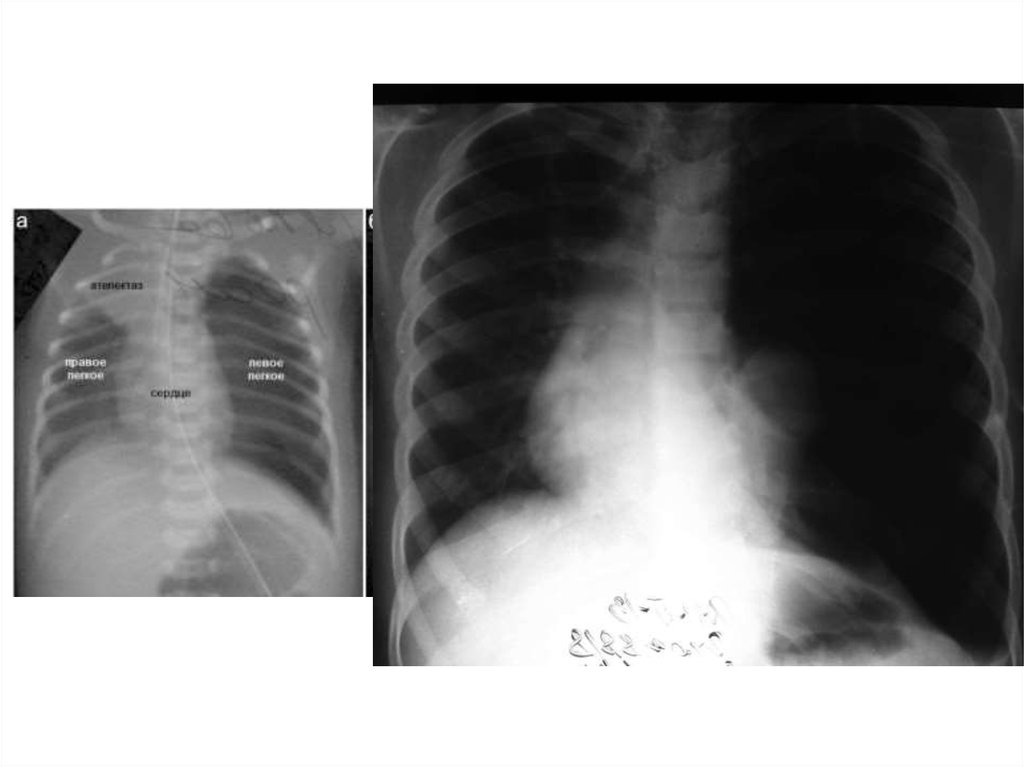

33. Дыхательная система Respiratory system

• Легкие новорожденного богаты кровеносными сосудами,

межуточной тканью и бедны эластической тканью. Лимфатические

щели и капилляры широкие. Вследствие этих особенностей легкие

более полнокровны, менее воздушны и эластичны, что создает

условия для возникновения застойных явлений и

развития инфекции.

• У новорожденных дыхание частое и поверхностной,

характерны аритмия и лабильность дыхания. Число

дыхательных движений у доношенного новорожденного

от 40 до 50—60 в 1 мин.

• Становление функции дыхания у новорожденных

происходит при участии легочного сурфактанта

(антиателектатического фактора). При недостатке

сурфактанта (например, при гипоксии) развивается

синдром дыхательных расстройств (СДР).